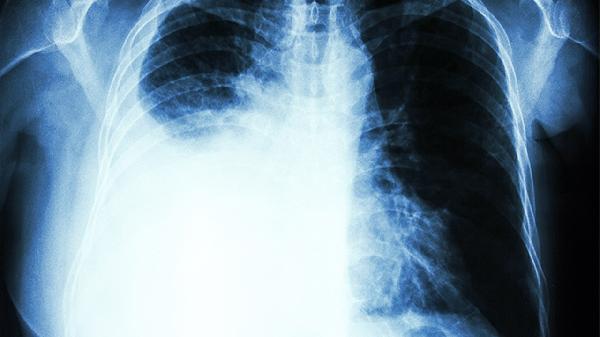

对于严重移位性骨折或合并内脏损伤者,需行胸骨钢板内固定术或钢丝环扎术。术后需住院观察1-2周,定期复查X线评估愈合情况。手术干预能有效恢复胸廓稳定性,降低畸形愈合风险。